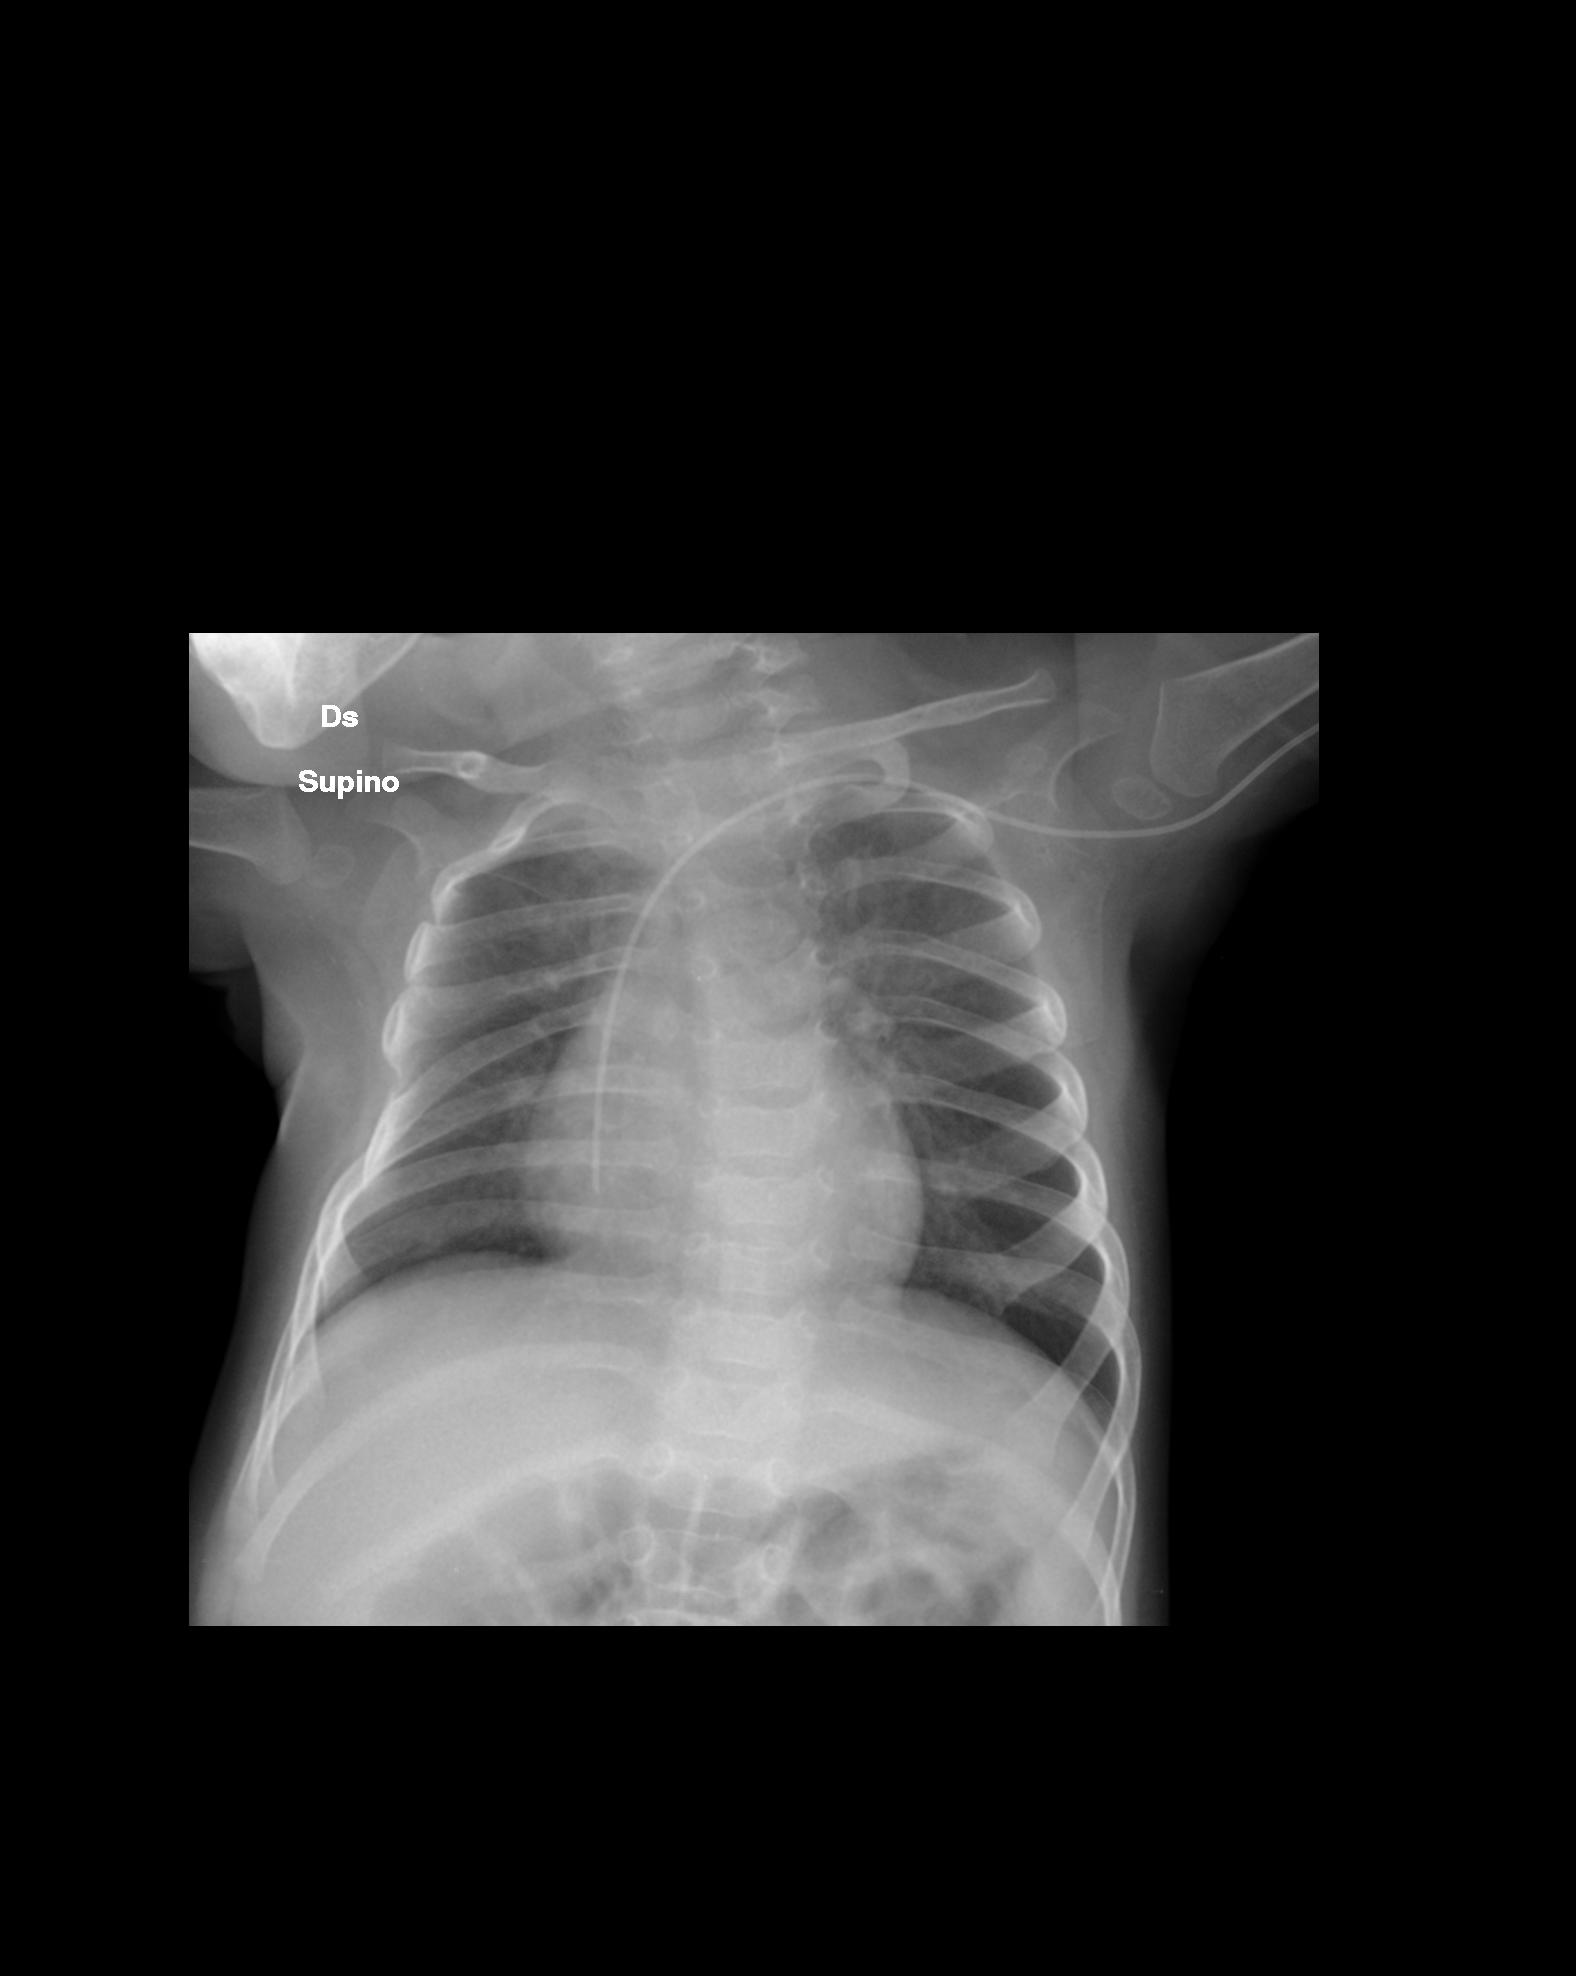

Nel corso della degenza in Rianimazione le condizioni generali del bambino vanno progressivamente migliorando. Sono comunque presenti rumori grossolani diffusi e persistenti su tutto l'ambito toracico. Dopo alcuni giorni la radiografia del torace, che fino a quel momento � progressivamente migliorata pur persistendo l'opacit� all'apice polmonare di destra (Figura 2), � assolutamente sconfortante, ed evidenzia una nuova opacit� al campo polmonare superiore di sinistra associata a broncogramma aereo in sede retrocardiaca sinistra con lieve deviazione mediastinica (Figura 3).

3. Opacit� al campo superiore di sinistra. Presente lieve

ipoespansione dell'emitorace di destra rispetto al controlaterale,

con dimorfismo del V arco costale di destra. Figura